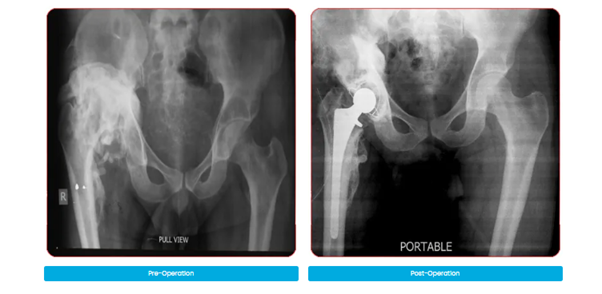

Complex Knee & Hip Replacement Surgeries

Our surgeons are highly experienced in handling complex cases like bow legs (varus), knock knees (valgus), or wind-swept legs, and have considerable expertise in revision joint replacement surgeries.